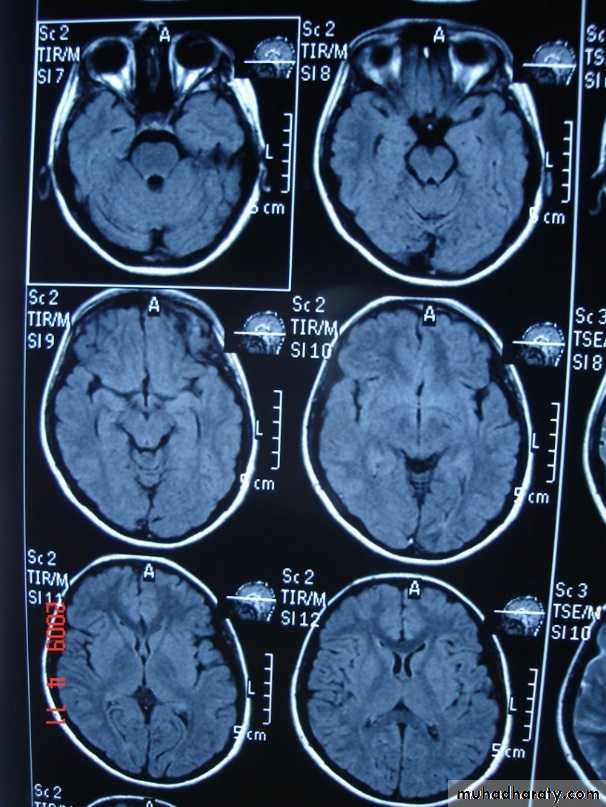

-MRI is more sensitive than CT in the demonstration of MS plaques.

- the most characteristic appearance is that of peri ventricular nodular Hyper intense lesions on T2 weighted images.

-the plaques are also well seen at the gray- white matter interfaces.

-MRI can even image lesions in the spinal cord , brainstem & cerebellum.

-contrast enhancement after giving gadolinium occurs in the acute phase indicating activity & in the chronic phase doesn't enhance.

-differential diagnosis :1-ischaemic lesions ,2-following radiotherapy , 3- in encephalomyelitis.